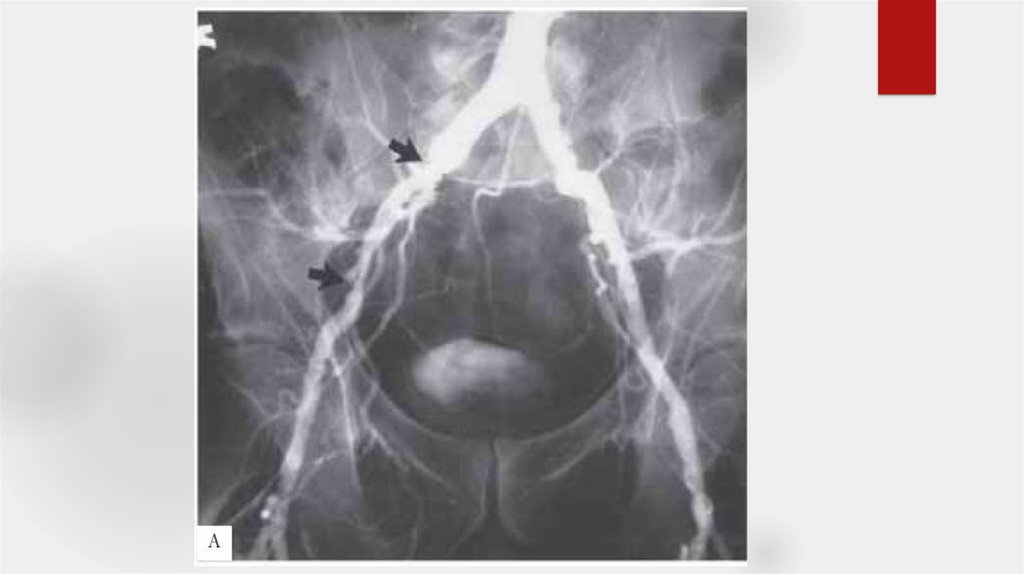

24. Оценка ангиограмм

Критерии:

- Окклюзии, их локализация

- Сегментарный уровень

- Степень

- Длинна пораженного участка

- Конфигурация и анатомия

- Количество пораженных артерий

- Морф.тип стеноза

- коллатеральное кровообращение